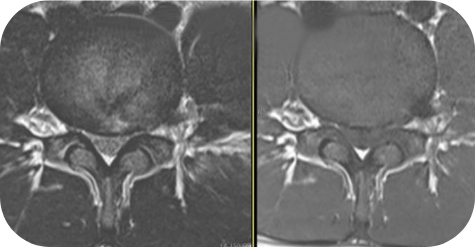

이 수술법이 처음 나온 지는 20년이 넘었습니다만 최근 들어 기기와 기술의 발전으로 각광을 받게 되었습니다. 피부에 약 7 mm 크기의 내시경을 넣어 수술을 하는 것으로 수술 후 회복이 매우 빠르다는 장점이 있습니다. 과거에는 터져 나온 디스크를 처리하지 못하는 한계를 보였으나 이제는 많이 발전하여 디스크의 여러 유형을 처리할 수 있어 수술의 성공률이나 환자의 만족도도 많이 높아졌습니다.

- 추간판탈출증